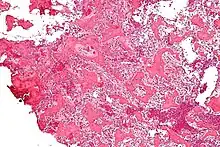

On histological examination, osteoid osteoma consists of a small (< 1.52 cm), yellowish-to-red nidus of osteoid and woven bone with interconnected trabeculae, and a background and rim of highly vascularized, fibrous connective tissue. Varying degrees of sclerotic bone reaction may surround the lesion. Benign osteoblastoma is virtually indistinguishable from osteoid osteoma. The usual appearance included a fibrovascular stroma with numerous osteoblasts, osteoid tissue, well-formed woven bone, and giant cells. The osteoblasts were generally small and regular in shape.[7]